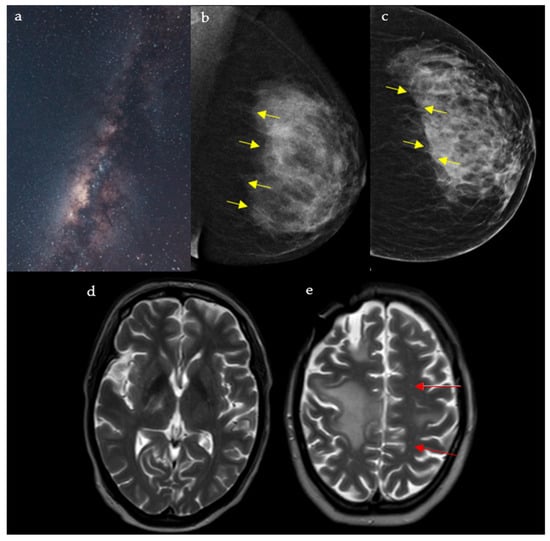

2.5. Milky Way Sign

2.5.1. On Breast Imaging

2.5.2. In Neuroimaging

- Xu, Y.; Miyake, K.K.; Liu, Y.I.; Downey, J.R.; Lipson, J.A.; Allison, K.H.; Ikeda, D.M. The Milky Way Sign: A New Diagnostic Finding of Ductal Carcinoma in situ on Digital Breast Tomosynthesis. Breast J. 2016, 22, 349–351. [Google Scholar] [CrossRef]

- Harvey, J.; Nicholson, B.; Cohen, M. Finding Early Invasive Breast Cancers: A Practical Approach. Radiology 2008, 248, 61–76. [Google Scholar] [CrossRef]

- Giess, C.; Frost, E.; Birdwell, R. Interpreting One-View Mammo- graphic Findings: Minimizing Call- backs While Maximizing Cancer Detection. Radiographics 2014, 34, 928–940. [Google Scholar] [CrossRef]

- Wijburg, M.T.; Witte, B.I.; Vennegoor, A.; Roosendaal, S.D.; Sanchez, E.; Liu, Y.; Martins Jarnalo, C.O.; Uitdehaag, B.M.; Barkhof, F.; Killestein, J.; et al. MRI criteria differentiating asymptomatic PML from new MS lesions during natalizumab pharmacovigilance. J. Neurol. Neurosurg. Psychiatry 2016, 87, 1138–1145. [Google Scholar] [CrossRef]

- Alleg, M.; Solis, M.; Baloglu, S.; Cotton, F.; Kerschen, P.; Bourre, B.; Ahle, G.; Pruvo, J.P.; Leclerc, X.; Vermersch, P.; et al. Progressive multifocal leukoencephalopathy: MRI findings in HIV-infected patients are closer to rituximab- than natalizumab-associated PML. Eur. Radiol. 2020, 31, 2944–2955. [Google Scholar] [CrossRef]